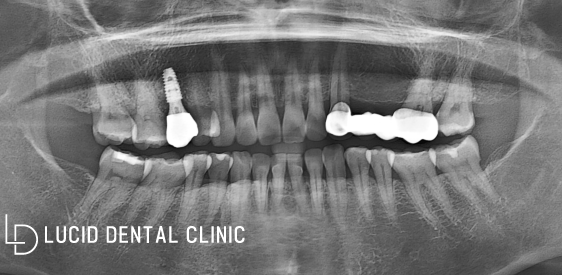

이제 체결된 어버트먼트를 제거하고

제작한 크라운을 올리기로 했습니다.

크라운은 지르코니아로 제작하여

심미성과 기능성을 모두 잡았는데요

그후 교합 높이를 조정해 드리고

연마 작업으로 마무리하였습니다.

이렇게 임플란트 수술 을

무사히 마칠 수 있었는데요